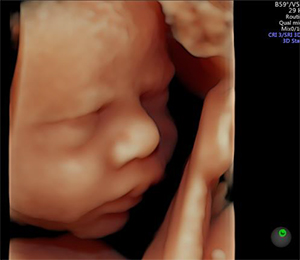

Voluson S10による胎児の3次元画像 |

「Voluson S10」は,Voluson E10とVoluson E8に採用されているプレミアム機種向けのシステムアーキテクチャ「Radiance System Architecture(ラディアンス・システム・アーキテクチャ)」で培った基盤技術をコンパクトなボディーに移植した「Voluson Core Architecture(ボルソン・コア・アーキテクチャ)」を採用した。このテクノロジーの搭載により,基本画質の向上,および心臓や血管の血液の流れをより繊細に装置のディスプレイ上で確認できる「カラードプラ」の感度向上を実現している。さらに,Voluson製品の強みである,3D/4D機能の性能も格段に向上。既に多くの施設で利用されているリアルな3D/4Dイメージング「HDlive」機能を始め,レンダリングのラインを自動でリアルタイムに最適化する「SonoRenderlive」機能,さらに,胎児の心臓の動きを再構築する「STIC(Spatio-Temporal Image Correlations)」機能を標準搭載するなど,周産期医療に必要な多くのアプリケーションを搭載し,日々の診療に貢献する。

正確に再現されたかのようなリアルな表現のサーフェス画像を表現し,仮想光源で陰影をつけることにより,さらなる立体感を実現した「HDlive」機能,胎児の心臓の撮影画像をボリュームデータとして 保存し,一定周期の繰り返し動作を行う対象に対して一周期分の3次元画像を再構築する「STIC(Spatio-Temporal Image Correlations)」機能,ボリュームデータ内の低輝度領域の数,容積,平均径を自動的に算出する「SonoAVCfollicle」(オプション)など, 周産期医療に特化したアプリケーションを豊富に搭載。